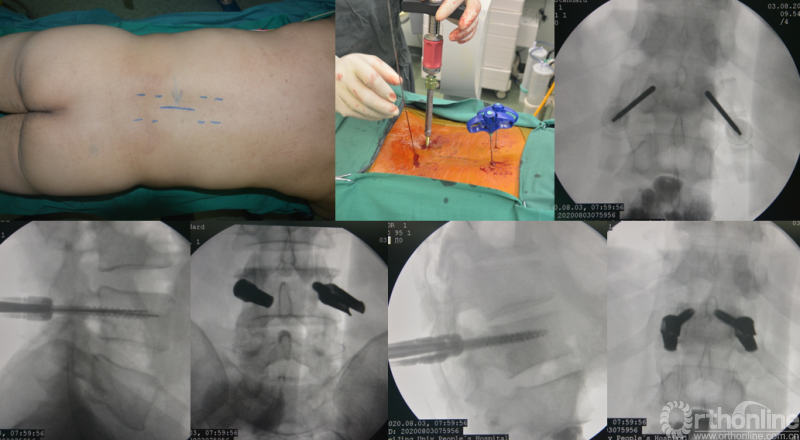

为进一步减少创伤,获得更好的综合疗效。骨采用经皮内固定的微创杂交技术,暨经皮内固定结合小切口分离手术,手术失血900ml,术后7天出院。

术中资料

经脊柱转移瘤专业评估,ESCC分级为Grade2,对放疗不敏感;SINS评分8分,中度不稳。Karnofsky功能状态评分90%,预计生存时间6个月。NOMS流程建议分离手术和SRS。

常规分离手术可进行360°脊髓减压,充分固定恢复脊柱稳定;但由于其暴露范围广泛,创伤较大,并不适宜患者当前治疗。